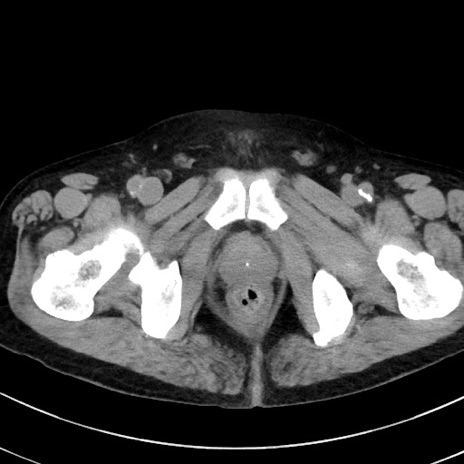

冠状断像